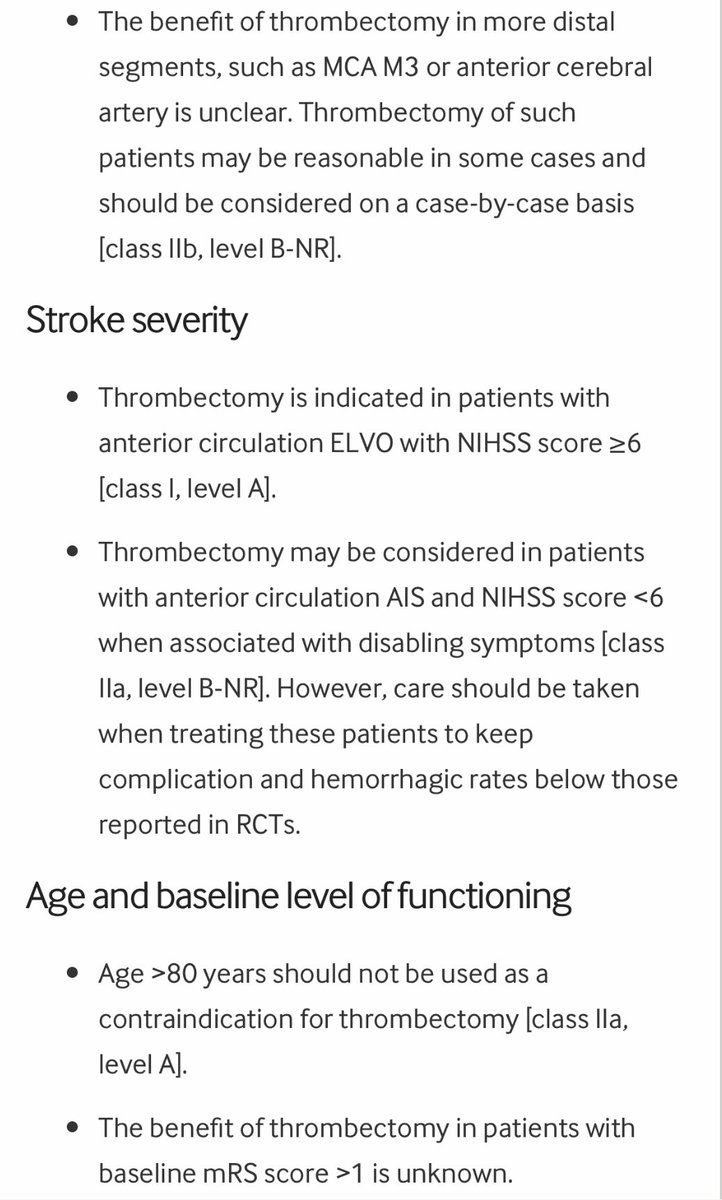

للاطباء المهتمين في علاج السكتات الدماغيه الحاده

Latest 2019 guidelines for acute stroke

ahajournals.org

Other recommendations attached 👇👇

Latest 2019 guidelines for acute stroke

ahajournals.org

Other recommendations attached 👇👇